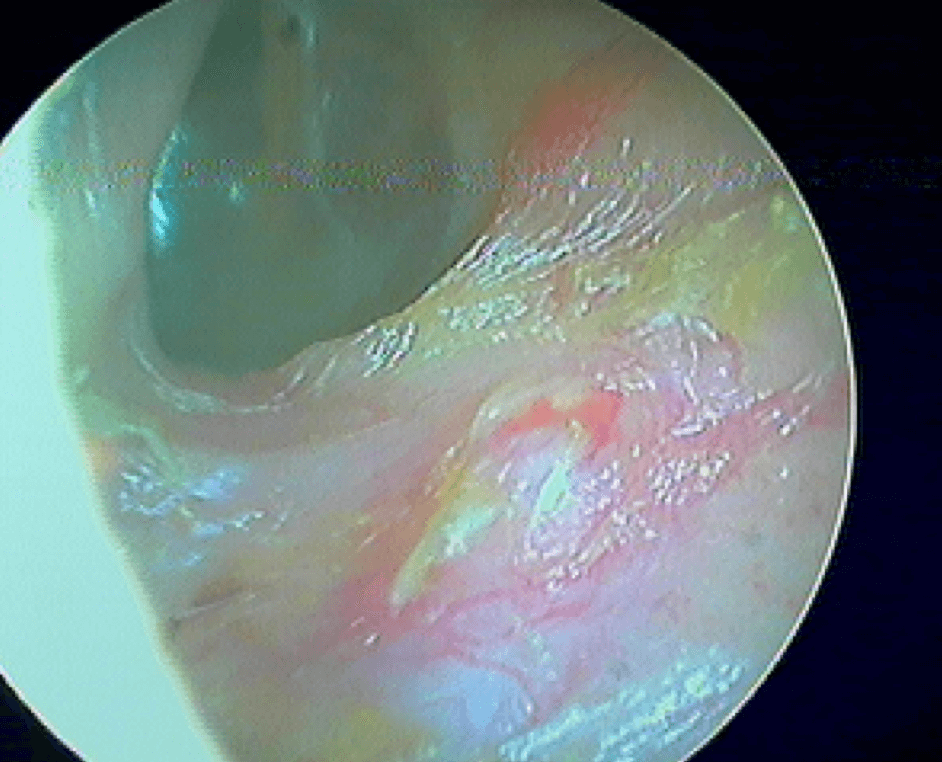

9 OTITE MOYENNE CHRONIQUE (OMC) NON CHOLESTÉATOMATEUSE

Perforation , otorrhée à répétition, otite muqueuse dans la caisse, lyse ossiculaire, rétraction tympanique. La limite entre l'otite atéléctasique perforée et l'otite moyenne chronique non cholestéatomateuse est souvent ésotérique...